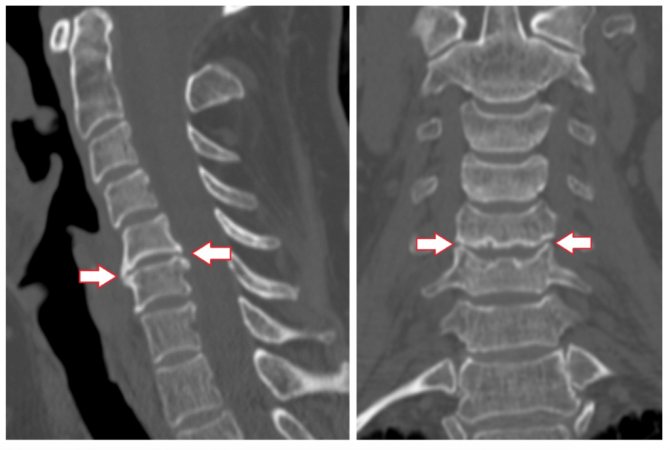

Поражение хрящевого диска и остеофиты на КТ

На основании клинической картины врач может заподозрить развитие патологии. Для достоверного определения характера, локализации и тяжести изменений необходимо сделать визуализацию позвоночника при помощи следующих методик:

- Рентгенография в прямой и боковой проекции.

- Компьютерная томография.

- Магнитно-резонансная томография.